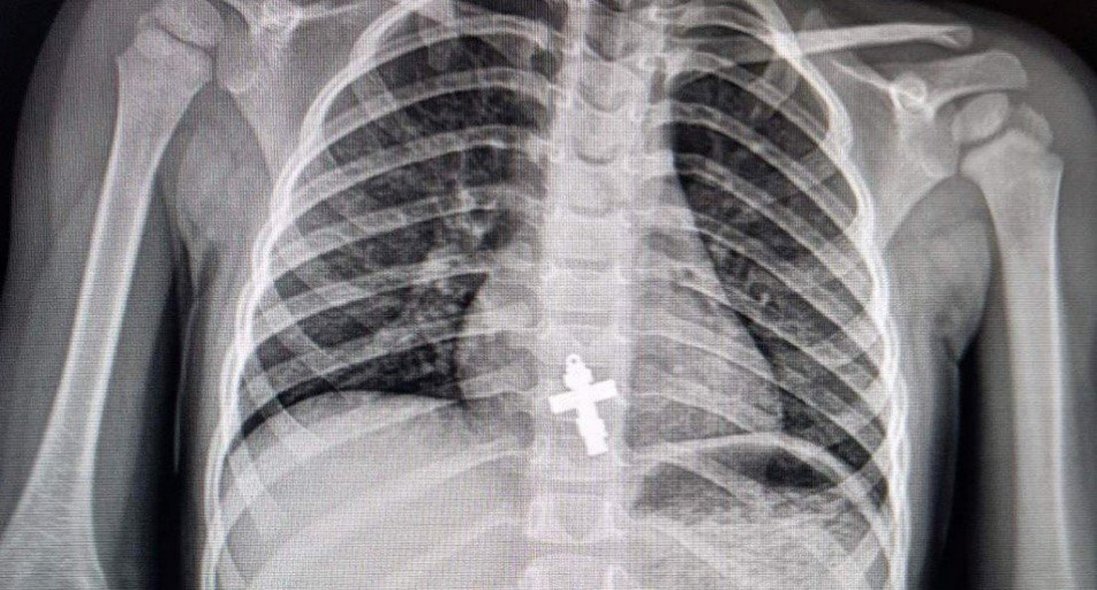

«Водночас, – розповідає хірург дитячий Василь Демчук, – клінічна картина не була типовою для апендициту. Після додаткових обстежень, зокрема рентгенографії, з’ясувалося, що у кишківнику дитини сторонні тіла».

Як розповідає лікар-ендоскопіст та хірург дитячий Олександр Сльозко, проковтування монет дітьми – поширене явище. Такі випадки трапляються регулярно, подекуди й до 10 на тиждень. У квітні лікарям також довелося ендоскопічно діставати з бронхів підлітків цвях та канцелярську кнопку, а зі стравоходу дворічної дитини – натільний хрестик.